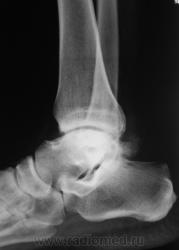

Пациент направлен на рентгенографию голеностопного сустава с диагнозом ДОА.

После внутрисуставного перелома вероятность доа оччень высока. Колгда была травма?

Травма была два года тому.

Похоже  на  остеохондропатию  блока  таранной  кости  +   ДОА.

Посттравматический артроз с кистовидной перестройкойлатерального мыщелка Субхондральное уплотнение исужение суст. щелей естьИ неконгруэнтность большеберцового эпифиза к таранной маленько просматривается?